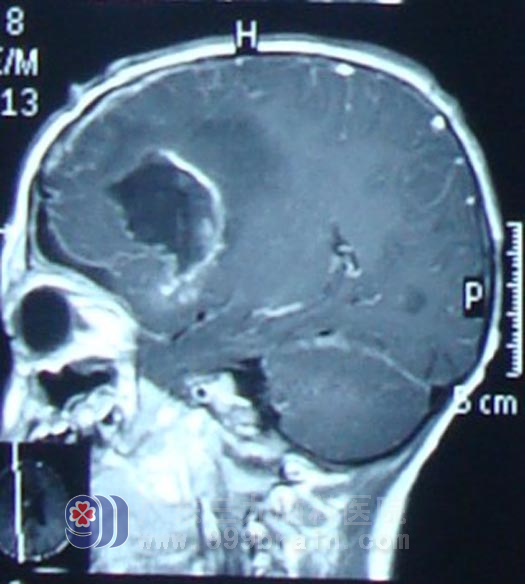

入院后积极完善术前相关检查,于2月11日在广东三九脑科医院神经外科行右额叶及基底节区肿瘤大部分切除术,术后病理示间变型室管膜瘤Ⅲ级。术后行同步放化疗,头部适形放疗完成54Gy,后再行几程辅助化疗后复查头颅MR显示强化及水肿范围明显缩小,康康精神状态良好,未诉不适。http://www.999brain.com/

术后